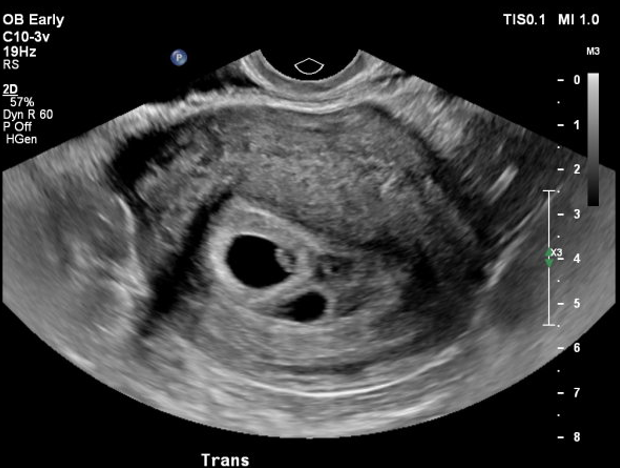

Qu'est-ce que l'échographie de datation ?

L’échographie de datation est une toute petite échographie que l’on effectue pour préciser la date de début de grossesse. Elle peut être utile ou si elle présente des saignements inexpliqués, si elle a des antécédents de grossesse multiple ou de grossesse extra-utérine.

L’échographie de datation peut être réalisée dès lors que l’on voit un sac ovulaire dans l’utérus, soit entre 5 et 9 semaines d’aménorrhée (soit entre 3 et 7 semaines de grossesse).